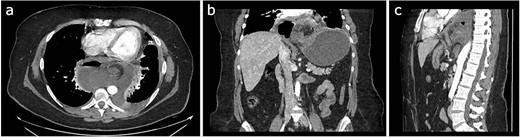

Initial treatment included intravenous crystalloid fluid repositioning, pain management, and antibiotic therapy. After diagnosing perforated gastric volvulus on a computed tomography (CT) scan, a diagnostic laparoscopy was performed. A hiatal hernia was identified with protrusion and twisting of the gastric body (Fig. 2). As the stomach body was reduced back to the abdominal cavity, a 1.5-cm perforation at the level of the greater curvature was detected. It was primarily sutured and covered with an omental patch (Fig. 3). The ischemic hernia sac containing the stomach was filled with food scraps and resected (Fig. 4). Laparotomy conversion was necessary due to hemodynamic instability attributable to the laparoscopic pneumoperitoneum. A 180° anterior fundoplication of the stomach (Dor’s Technic) associated with diaphragmatic raffia was performed. Gastric air leak testing was negative and intraoperative endoscopy showed no other defects on the gastric wall.

Laparoscopic view demonstrating an approximately 1.5-cm lesion at the level of the greater curvature of the stomach.